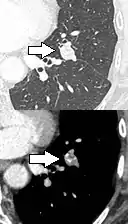

If there is an intermediate risk of malignancy, further imaging with positron emission tomography (PET scan) is appropriate (if available). It can be done simultaneously as a CT scan in the form of PET-CT. Around 95% of patients with a malignant nodule will have an abnormal PET scan, while around 78% of patients with a benign nodule will look normal on PET (this is the test sensitivity and specificity).[15] Thus, an abnormal PET scan will reliably pick up cancer, but several other types of nodules (inflammatory or infectious, for example) will also show up on a PET scan. If the nodule has a diameter of less than one centimeter, PET scans are often avoided because of an increased risk of falsely normal results.[15][16][17] Cancerous lesions usually have a high metabolism on PET, as demonstrated by their high uptake of FDG (a radioactive sugar).

PET-CT of a tuberculoma.